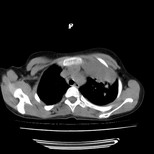

女,12岁,前期发热,咳嗽,无痰,经头孢抗炎无效。ct右肺上叶实变影.5天后公布病理结果。以下是2010-2-13ct片

定位肺外,年龄小,还是先考虑畸胎瘤,左上肺膨胀不全并炎症。

鉴别:内胚窦瘤恶性程度高,有胸水;淋巴瘤、胸腺瘤、sftp等年龄大;异物上叶少见,无肺气肿及纵膈偏移不支持;炎症定位不考虑肺内所以排除。

左前上纵膈可见大块影,与大血管关系密切,邻近肺少许炎症,考虑左前上纵膈占位,胸腺瘤或畸胎瘤,并左上肺膨胀不全。

经过胸部穿刺活检为支原体感染。以下示抗支原体感染30天后所见,病灶明显缩小,临床症状消失: